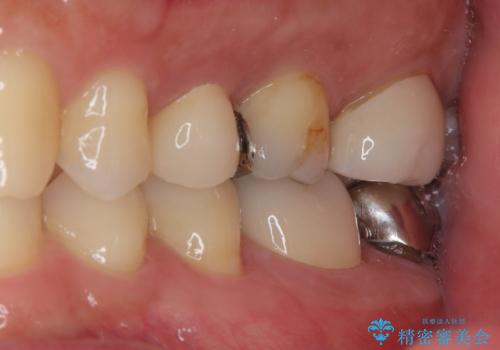

拡大鏡視野下で、セラミックの詰め物、虫歯の除去を行い、オールセラミッククラウンに適した形に整えました。

歯と歯茎の間に圧排糸と言われる糸を入れてシリコーン印象材にて型どりをしました。

見た目、機能面ともに満足していただけました。